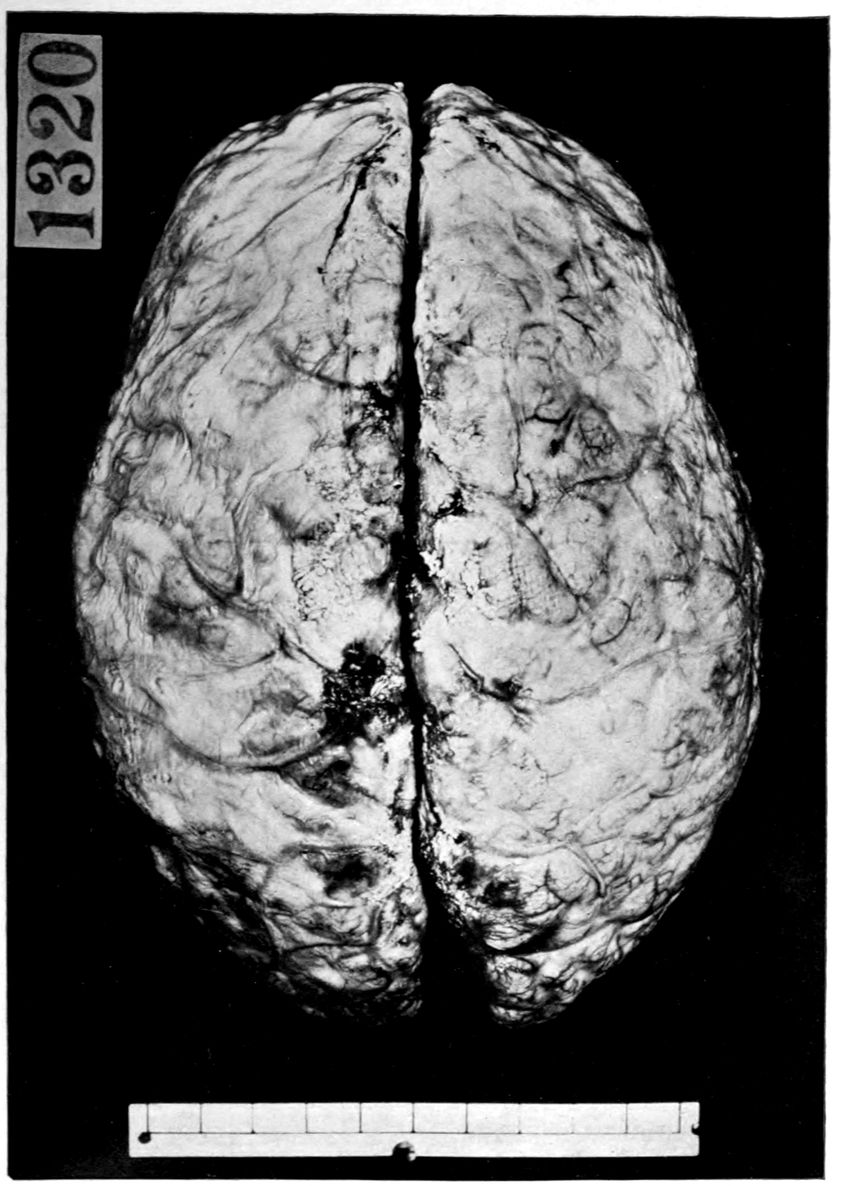

Head: Scalp closely adherent to calvarium. Calvarium heavy without diploë. Dura adherent to calvarium in bregmatic region. Sinuses contain liquid blood. Arachnoidal villi in considerable quantity. Pia mater contains considerable clear fluid and shows diffuse haziness and focal thickenings. The diffuse haziness is almost universal and is best marked over the superior surface of the cerebellum. The focal thickenings are of general distribution over the veins of the sulci on the superior surface of the brim and are heaped up to form considerable linear mounds near the region of the arachnoidal villi. The superior surface of the cerebellum is traversed by similar linear mounds of fibrous tissue running at an angle to the laminæ. There is no notable increase of fibrous tissue at the base.

Brain: Weight 965 grams. The sulcation is roughly symmetrical except in the occipital poles where there is unusually rich and complex but shallow sulcation. The cortical substance is everywhere firmer than normal, but the sulci fail to flare notably. In a few places there is a focal increase of consistence of still greater degree with apparent local hypertrophy (or gliosis with increase of substance). These foci are in the right second temporal gyrus (3 cm. in diameter) and in the left first temporal gyrus (of same size but somewhat less firm) and are of a whitish, waxen appearance, being visible several feet away by reason of their color and apparent encroachment upon the adjacent sulci. The foci are sharply limited by the sulci laterally, but pale out gradually before and behind.

The convolutions of the vertex show another type of lesion. The tissue of the greater part of the vertex resembles that of the flanks and base in being firmer than normal and of a grayish pink color. Behind the fissure of Rolando on the right side and behind the anterior limits of the ascending frontal region on the left 47side the brain tissue of the vertex becomes suddenly still firmer and of a yellowish gray color. This lesion disappears gradually into the occipital microgyria behind and the gyri gradually lose their yellowish tint. The lesion fades away gradually so that it fails to involve the temporal convolutions.

The cerebral tissue cuts firmly and smoothly. The tissue of the frontal region is a little edematous. The white matter is of a normal appearance. The ependyma of all the ventricles is somewhat sanded. The fourth ventricle is most affected.

The cerebellum is not edematous and is as firm as the normal olivary bodies. The cerebellar hemispheres are symmetrical and of a normal appearance, save that the laminæ are slightly narrower than usual and very compactly set. The color, where not obscured by the haziness of the pia mater, is of a grayish pink somewhat suggestive of freshly tanned shoe leather. The substance cuts smoothly and firmly. The dentate nuclei are unusually firm. The pons is small, but of the usual color. Lower structures normal except the cord which is small and shows curious deviations from the normal markings. The posterior horns and gray commissure are at many levels the only structures to preserve the normal gray appearance, so that the H or butterfly appearance is replaced by a crescent. At these levels, traces of gray matter often stand out in the loci of the anterior horns.

The important anatomical diagnoses in the nervous system are as follows:

Atrophy of cerebrum, 965 grams (there is of course a question whether we are not dealing with a degree of cerebral hypoplasia).

Focal scleroses of cerebrum, suggesting the tuberous scleroses of Bourneville.

Occipital microgyria.

Cerebral and cerebellar gliosis.

Chronic ependymitis.

Gliosis of the gray matter of the spinal cord.

Chronic diffuse and focal leptomeningitis.